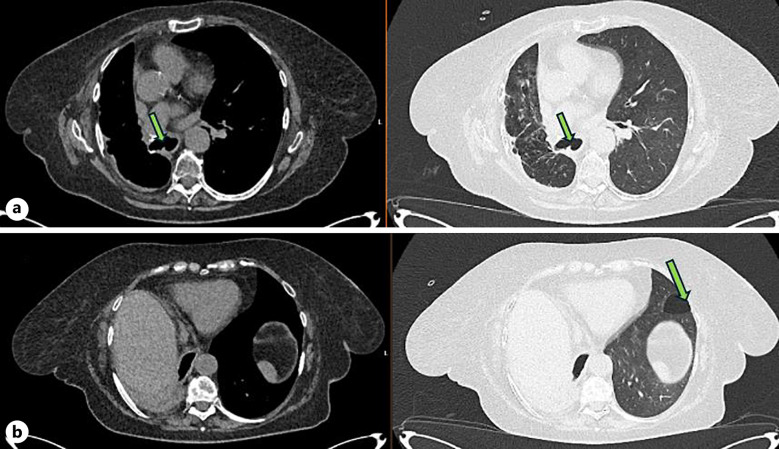

Case presentation: This report discusses the case of a 71-year-old female who presented with shortness of breath and a continuous cough secondary to a fistula between the oesophagus and right bronchus on the background of squamous cell carcinoma (SCC). This patient was seen by oncologists for the treatment of her lung cancer after right middle and lower lobe lobotomies, which was then treated with radiotherapy. On admission, a computed tomography scan revealed that the patient had a BOF due to therapeutic radiotherapy for SCC. She underwent intervention from the gastrointestinal and respiratory physicians to treat the BOF. Oesophageal stent placement was performed for treatment; however, the BOF remained patent, so a bronchial stent was considered for insertion. While the patient was awaiting the bronchial stent, she died.